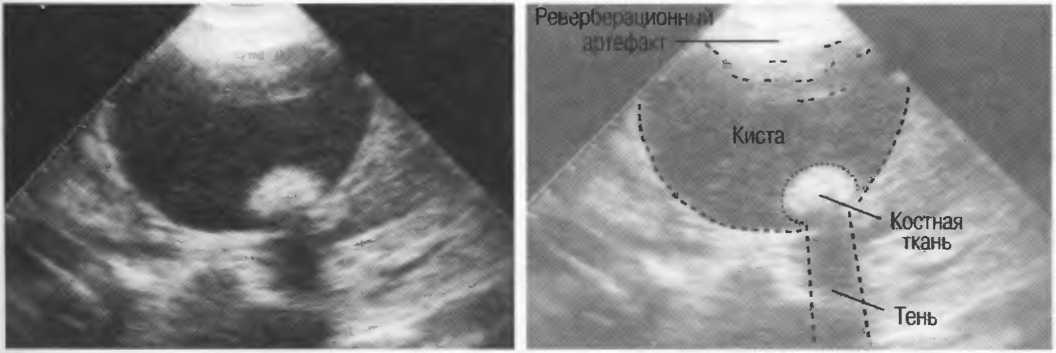

Тени

Кости, камни и кальцинаты дают акустическую тень. Ультразвук не может проходить через кость, если она только не очень тонкая (как, например, кости черепа у новорожденного). При необходимости рассмотреть структуры, расположенные глубже, необходимо использовать различные углы наклона датчика (рис. 17а,б).

Рис. 17а. Большая акустическая тень за камнем в желчном пузыре.

Рис. 176. Это изображение почки частично экранировано тенью ребра. Сканирование в различные фазы дыхания поможет визуализировать всю почку целиком, «вывести» ее из-под ребра.